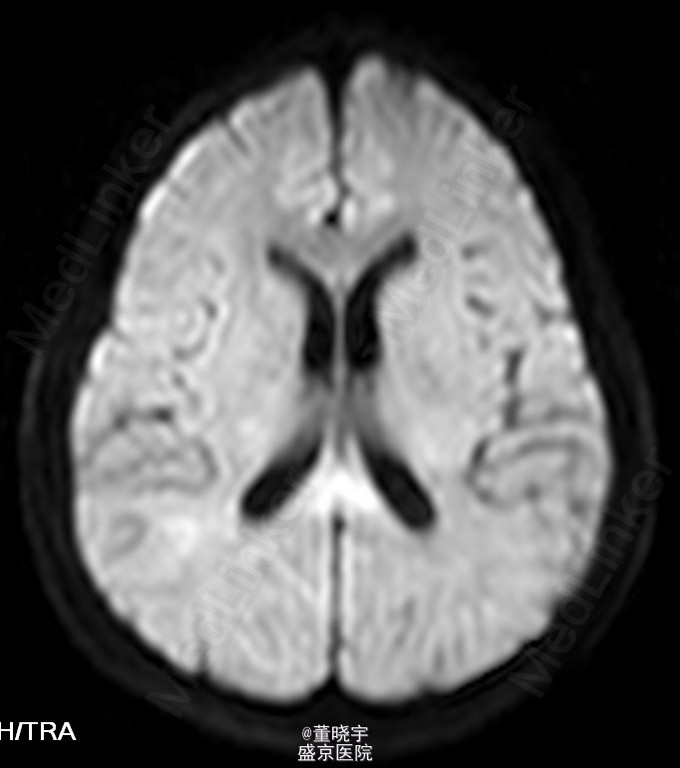

神经系统专科查体:神清语明,双瞳等大正圆,D=4.0mm,对光反射迟钝,视力丧失,双眼球各向运动充分,无复视及眼震,额纹对称,双侧鼻唇沟对称,伸舌居中,转颈有力,四肢肌力Ⅴ级,肌张力正常,双上肢指鼻准确,双下肢跟膝胫试验稳准,BCR L++R++, TCRL++R++,PSRL++R++,Babinski征L+R+,Hoffmann征L-R-,颈强,双掌颏反射(+)。 辅助检查:腰穿压力200mmH2O,细胞总数28*10^6/L,白细胞24*10^6/L,氯化物118.0mmol/L,糖2.41mmol/L,蛋白2.1g/L。 视觉诱发电位:双侧视通路传导障碍。 颅脑MRI见上。 核抗体(ANA)阳性;抗SS-A及抗SS-B抗体均阳性;IgG、IgA升高;补体 C3、C4下降。

诊断:原发性干燥综合征合并中枢损害 处理:静脉点滴丙种球蛋白治疗,临床症状稳定后出院口服强的松片10毫克/天。

半年后患者再次入院复诊,复查颅脑MRI提示新增病灶,但风免相关化验未见改变,急性长期口服激素治疗。 讨论:原发性干燥综合症(pSS)是一种以唾液腺和泪腺腺体淋巴细胞浸润和破坏为特点的自身免疫性疾病,临床主要表现为眼干、口干。腺体外表现主要是由于类似的单核细胞浸润或血管炎引起。CNS-SS的发病率及其颅脑MRI表现目前仍存在争议,有文献报道CNS病变发生率为0%-60%[1]。既往的一个400例患者大样本研究发现,只有1%患者合并CNS并发症。 CNS-SS的临床表现多样,脑部病变包括局灶性和弥漫性病变,局灶性病变主要表现为局部感觉和运动异常、失语、癫痈发作、构音障碍和视觉减退等;弥漫性病变主要表现为亚急性或急性脑病、无菌性脑膜脑炎、心理障碍和认知障碍等。中枢神经系统病变多隐匿起病,少部分患者呈急性或亚急性起病,部分患者同时合并有周围神经系统损害,加上部分pSS患者以中枢神经系统损害为首发症状,使得临床症状表现多样,诊断困难,极易误诊、漏诊并延误治疗。 目前对于pSS合并中枢神经系统病变治疗还没有统一的方案,大剂量激素治疗是目前临床中常用的方法之一,也有报道对于激素效果不佳的患者合并应用环磷酰胺也收到了不错的效果。静脉注射丙种球蛋白(IVIg)也是免疫相关的中枢神经系统病变常用治疗手段之一,尽管外文报道IVIg对于pSS引起的周围神经病变效果明显。